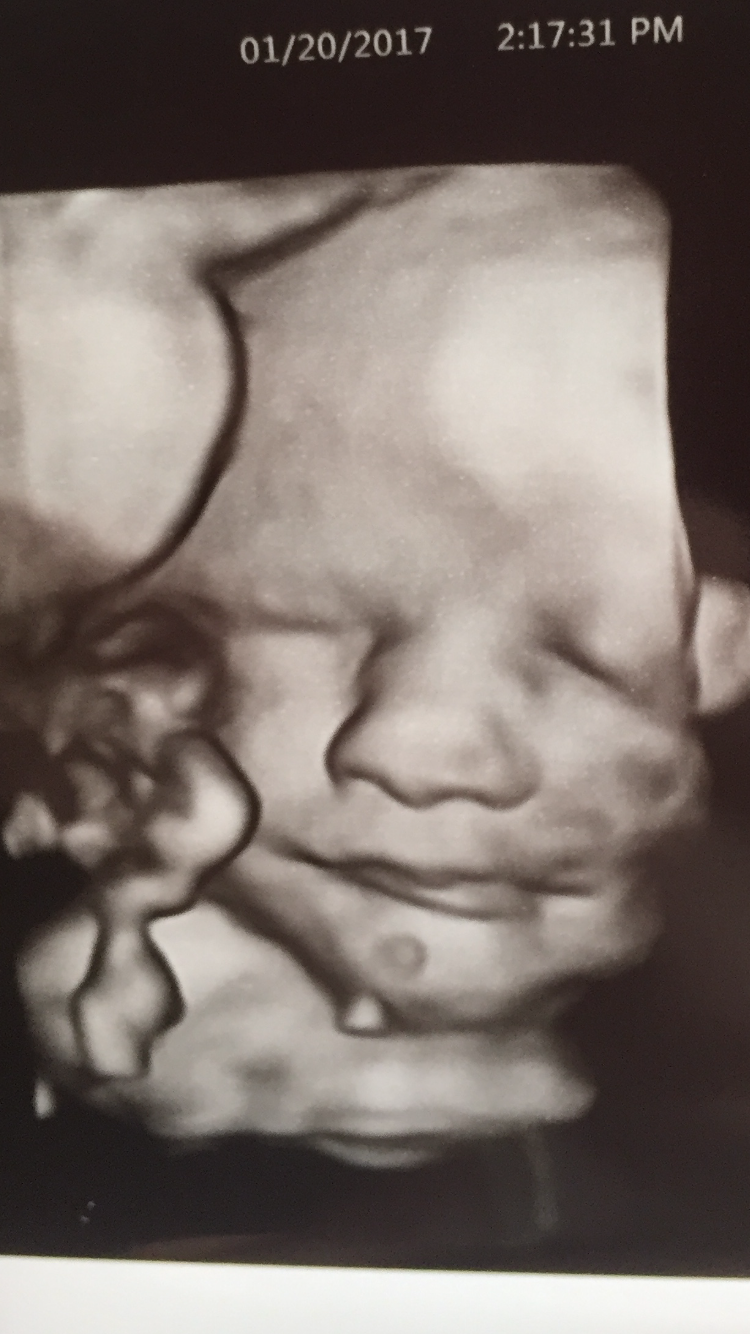

35 week look at Baby Boy! <3

Look

IMG_7943.PNG

Look at that sweet face! Hi baby!!!! He's a cutie for sure!

He does have a sweet face- This would be a perfect post for the AW Ultrasounds thread!